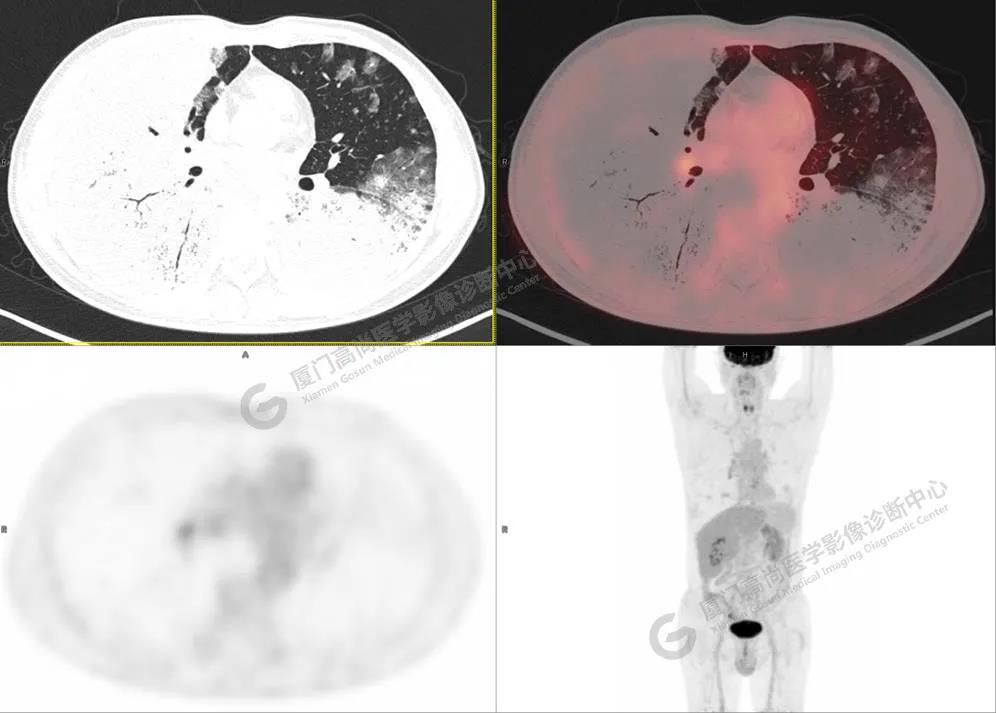

PET/CT影像圖

圖1

PET/CT所見(jiàn):雙肺大片實(shí)變影及磨玻璃影,部分呈地圖樣改變,累及右肺尖,部分放射性攝取輕微增高,SUVmax 1.77,其內(nèi)見(jiàn)多發(fā)支氣管充氣征象。

影像診斷: 雙肺大片實(shí)變影及磨玻璃影,大部分代謝不高,局部代謝輕微增高,考慮肺泡蛋白沉積癥,建議病理學(xué)檢查或肺泡灌洗物檢查。